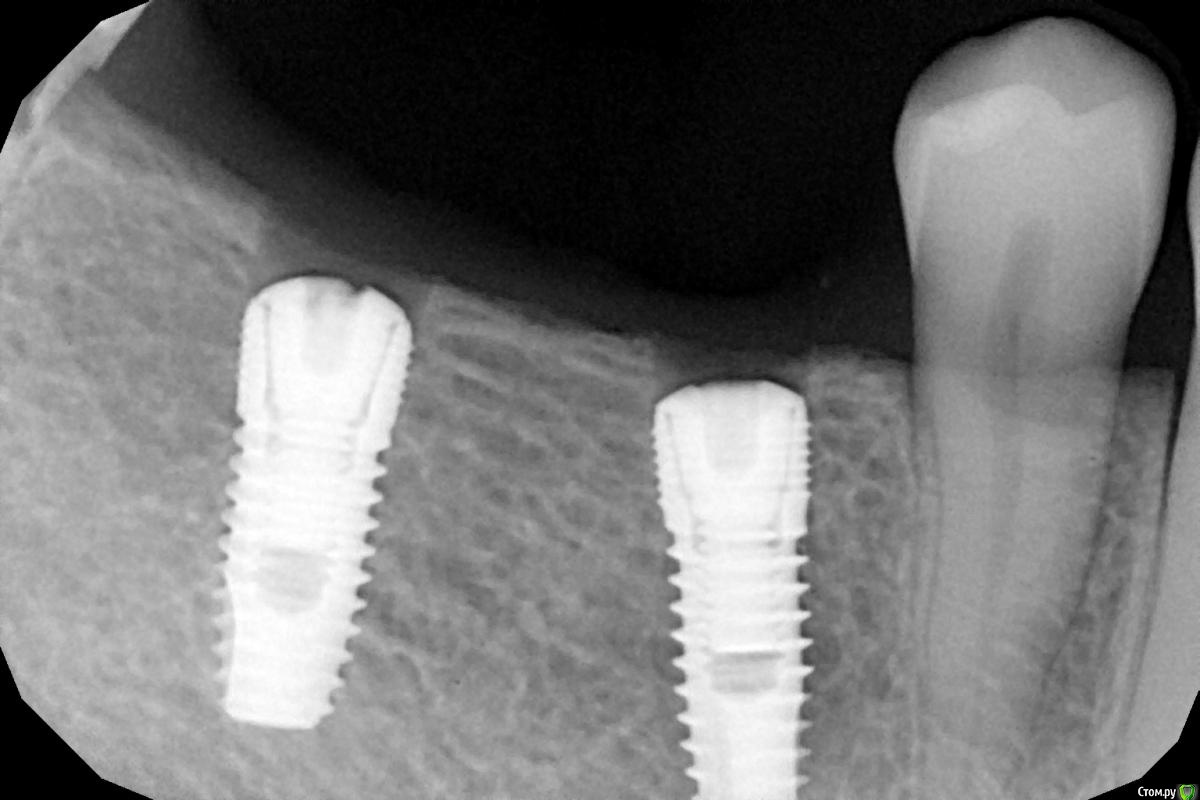

Женька Опубликовано 28 ноября, 2020 Поделиться Опубликовано 28 ноября, 2020 (изменено) Приветствую коллеги. В общем три недели назад 07.11.20 установил пациентке 2 имплантата в позиции 45-46. Гребень по ширине был около 6.5мм в области 4.5 и около 7.2мм в области 4.6 (с учётом заглубления на 1.5-2мм). Это была наверное первая имплантация во время которой я чувствовал себя спокойно и расслабленно. Всё прошло хорошо, немного покопался с непосредственным введением имплантатов, тк никак не хотели топиться на нужные 1.5мм. Поэтому пробовал методику с выкручиванием на пару витков и снова закручиванием. Особого толку не получил, потому взял финальную фрезу и чуть углублял ложе. Так несколько раз, тк боялся всё-таки немного что задену менталис и нлн. Ввиду того, что биотип у пациентки тончайший и язычно было совсем-совсем тонко - заглушки и швы. Назначил нпвс, ванны хг, аб терапию. Но на утро следующего дня пациентка сказала, что чувствует себя шикарно, решили что нпвс оставим, а аб терапию применять не будем (и грешу что в этом мою ошибка).Через неделю сняли швы, всё отлично.Спустя два дня после снятия начались какие-то "костные" боли, как говорит пациентка в области 4.5 импланта. Которые то отпускают, то снова наплывают. На 4.4 есть дефект твердых тканей (на фото виден), но судя по всему беспокоит не он .Пальпация вестибулярно в проекции 4.5 импланта болезненна, небольшая гиперемия, отёка нет. Гигиену пациентка запустила, тк боялась туда залезать и чистить. Снимки прилагаю первые два от 07.11, два последующих 28.11. Ну и внутри ротовые день операции и сегодняшние числа.Похоже 4.5 на выход? своими "туда-сюда" наверняка я нагрел всё что можно... снова расстройство в той работе, где накосячить предельно сложно... Добавка: пить аб ведь сейчас уже бесполезно? Изменено 28 ноября, 2020 пользователем Женька Ссылка на комментарий

Женька Опубликовано 28 ноября, 2020 Автор Поделиться Опубликовано 28 ноября, 2020 (изменено) Какой торк получили?45Вы тоже видите заглушки светят? Изменено 28 ноября, 2020 пользователем Женька Ссылка на комментарий

колесников Опубликовано 28 ноября, 2020 Поделиться Опубликовано 28 ноября, 2020 (изменено) Имплант 13 мм? Зачем? При планировании видно, что он упирается апексом в кортикалку. По этому и поставить не могли сразу. Торк 45. Если имплант плотно контактирует с компактной пластинкой,она резорбируется окончато,со всеми вытекающими. Стоило выбрать имплант 8.5мм. Если притопили имплант,зачем поставили заглушку? Имплант зарастёт придётся выпиливать ,откапывать заглушку,ломать то что наросло непосильным трудом. Хороший торк-ставьте рабочий фдм. Сомнения-мелкий фдм или заглушка +1. Рекомендую сделать контрольный кт и поставить фдм Изменено 28 ноября, 2020 пользователем колесников 5 Ссылка на комментарий

Женька Опубликовано 29 ноября, 2020 Автор Поделиться Опубликовано 29 ноября, 2020 Я бы сейчас сделала три вещи :дала курс антибиотика шикарной женщине,гигиену навела бы во рту или хотя бы в этой области,депульпировала премоляр.Чтобы прикрыться со всех сторон. Выждать. Вынуть всегда успеется.А потом.. может,там уже формики просятся?Три недели, не рановато ли? По поводу премоляра, терапевта напрягу. А на каком режиме Вы закручиваете/выкручиваете?20оборотов на торке 30, далее руками динамометрическим ключом. Имплант 13 мм? Зачем? При планировании видно, что он упирается апексом в кортикалку. По этому и поставить не могли сразу. Торк 45. Если имплант плотно контактирует с компактной пластинкой,она резорбируется окончато,со всеми вытекающими. Стоило выбрать имплант 8.5мм.Импланты 10мм каждый, разметка на планировании - глубина препарирования с учётом заглубления. Проблема то как раз в области 4.5 импланта, там нет такого контакта с кортикой апикально, а область шейки хорошо развальцевал кортикальной фрезой. 4.6 где как раз контакт кортикальный спокоен. Если притопили имплант,зачем поставили заглушку? чтобы избежать проблем как в предыдущем моём случае, где тоже было тонко язычно. Потому хотел на этапе раскрытия работать с десной и язычно перемещать объём. http://forum.stom.ru/topic/40254-otsrochennaia-implantatciia/ Сомнения-мелкий фдм или заглушка +1. что значит заглушка +1? Если сейчас залезть и выкрутить заглушки не велики ли риски прокручивания имплантата...ведь на 3-5 недели самая большая потеря первичной стабильности происходит. Ссылка на комментарий

Irouil Опубликовано 14 декабря, 2020 Поделиться Опубликовано 14 декабря, 2020 Ну и где тут язычно передавленная кортикалка? Меня смущает только картина в области верхушки симптомного винта, ну и заглубление Я бы дождался уже срока интеграции Ссылка на комментарий

Женька Опубликовано 14 декабря, 2020 Автор Поделиться Опубликовано 14 декабря, 2020 Ну и где тут язычно передавленная кортикалка? Меня смущает только картина в области верхушки симптомного винта, ну и заглублениеНе знаю, я про язычную кортику не говорил. Меня тоже смущает... и в области соседа такого фона (а это не фон я уверен) нет... А с заглублением что не так? по прицелам там 1.5-2мм, на кт почему-то этих мм вообще нет и как будто крестально стоят Ссылка на комментарий